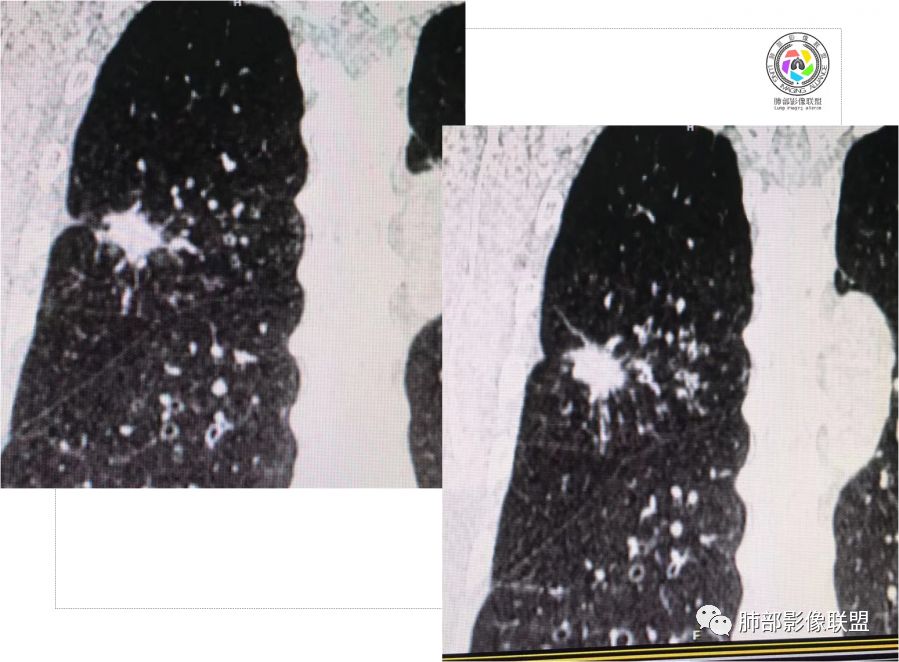

胸CT示病变位于右肺上叶,右肺上叶前段支气管壁不规则增厚狭窄、远端扩张。右肺上叶后段实变影,纵隔窗实变内可见钙化灶,可见支气管引流征,引流支气管壁明显增厚,边缘可见短硬毛刺,胸膜牵拉,u型征,周围可见卫星灶,并可见支气管扩张及其管壁增厚;病灶整体存在膨胀性生长。考虑良性病(结核)变基础上合并癌变,腺癌?

患者中老年男性,咳嗽喘息半年。查体双肺闻及哮鸣音。胸部CT:右肺上叶后段不规则结节灶,可见长毛刺、胸膜牵拉、分叶及钙化征象,周围见点片状卫星灶,近端支气管壁增厚,呈支气管爬行征。综合考虑结核。鉴别恶性病变。

中老年男性,右肺上叶不规则团块状病灶,深分叶、长软毛刺,内部见空泡、多发钙化,相邻支气管增厚,考虑病变来源于气道,首先考虑结核,有空泡,这个腺癌多见,需要鉴别。

中老年男性,右肺上叶不规则团块状病灶,深分叶、长毛刺,内部见空洞(近心侧)、钙化,相邻支气管增厚,有结核背景,首先考虑结核,腺癌需要鉴别。

3.本例病灶影像表现为:右肺上叶后段不规则结节灶,病灶整体存在膨胀性生长,可见毛刺、胸膜牵拉、分叶及钙化征象,近心端小空洞,周围见点片状卫星灶并出现磨玻璃影,近端支气管壁增厚,管腔扩张,既有恶性征象,也有结核的征象。南边老师考虑结核与腺癌同时存在,但遗憾的是缺乏增强扫描图像,亦未提供结核相关辅助检查结果。